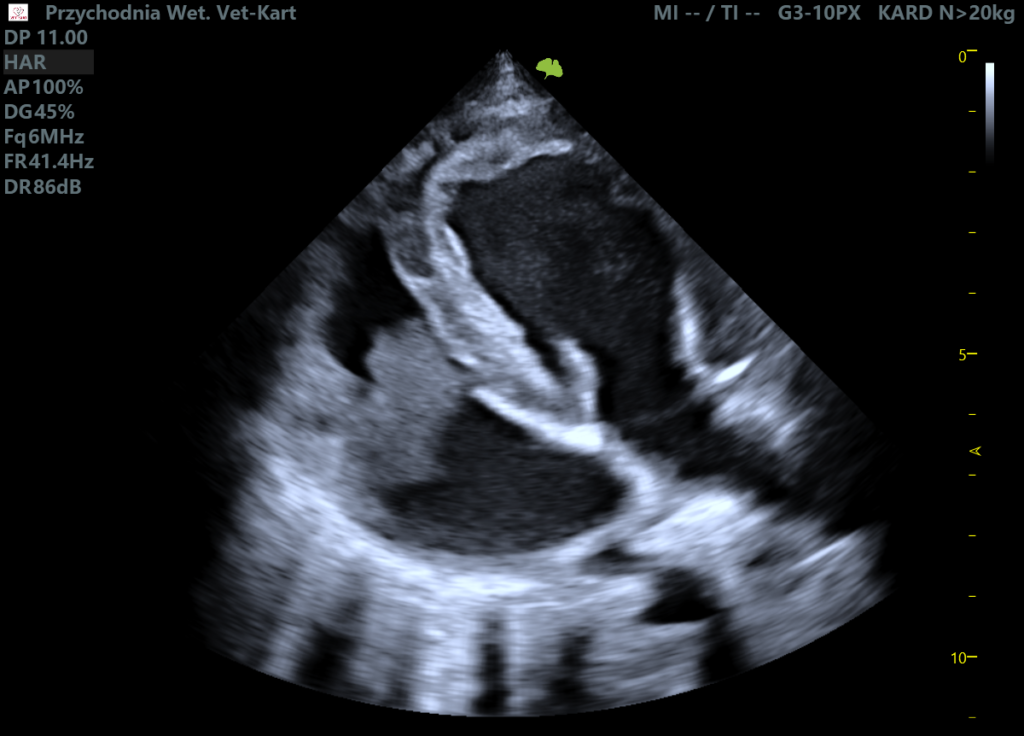

Wykonano badanie echo serca:

• niewielką niedomykalność mitralną

Kluczowym znaleziskiem była dobrze zdefiniowana, niejednorodna, hipoechogenna względem wsierdzia zmiana o wymiarach 4,4 × 3,3 cm, zlokalizowana na wysokości zastawki trójdzielnej, związana z jej płatkiem/pierścieniem. Masa poruszała się synchronicznie z ruchem zastawki i powodowała częściową obstrukcję.